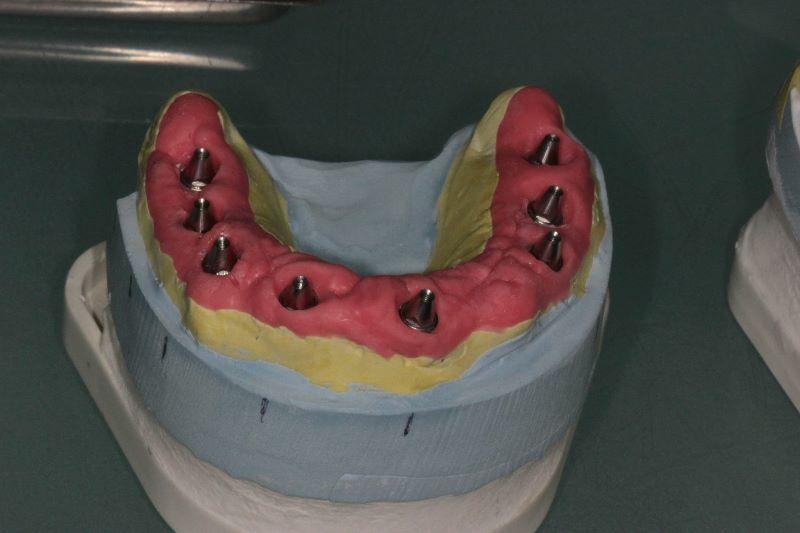

Пошаговое руководство по установке съёмного протеза на импланты